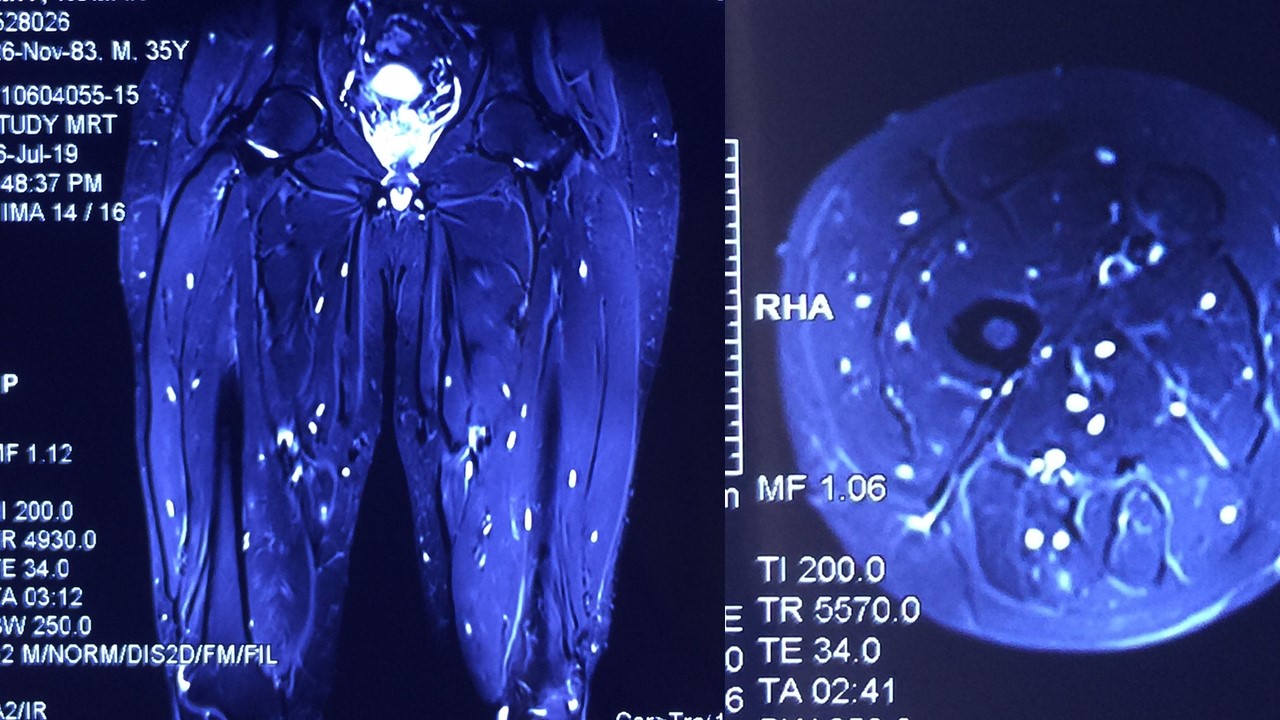

Disseminated cysticercosis (tapeworm)in a vegetarian male

Disseminated cysticercosis (tapeworm) in a vegetarian male

Prahlad K Sethi, MD and Nitin K Sethi, MD,

A 35-year-old vegetarian man presented with a generalized convulsion. MRI brain showed extensive cysticerci lesions involving the bilateral supra and infra-tentorial brain parenchyma, myofascial planes of the face, neck, floor of mouth, parotid glands and left orbital extraocular muscles (figure 1). MRI thigh showed diffuse cysticerci involving multiple muscles (figure 2). Disseminated cysticercosis can occur in vegetarians and non-pork eaters due to fecal-oral contamination of food with Taenia solium eggs from tapeworm carriers1.